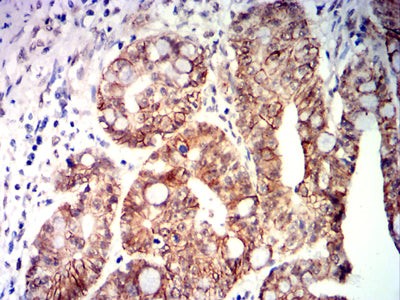

Immunohistochemical analysis of paraffin-embedded human rectal cancer tissues using CDX2 mouse mAb with DAB staining.